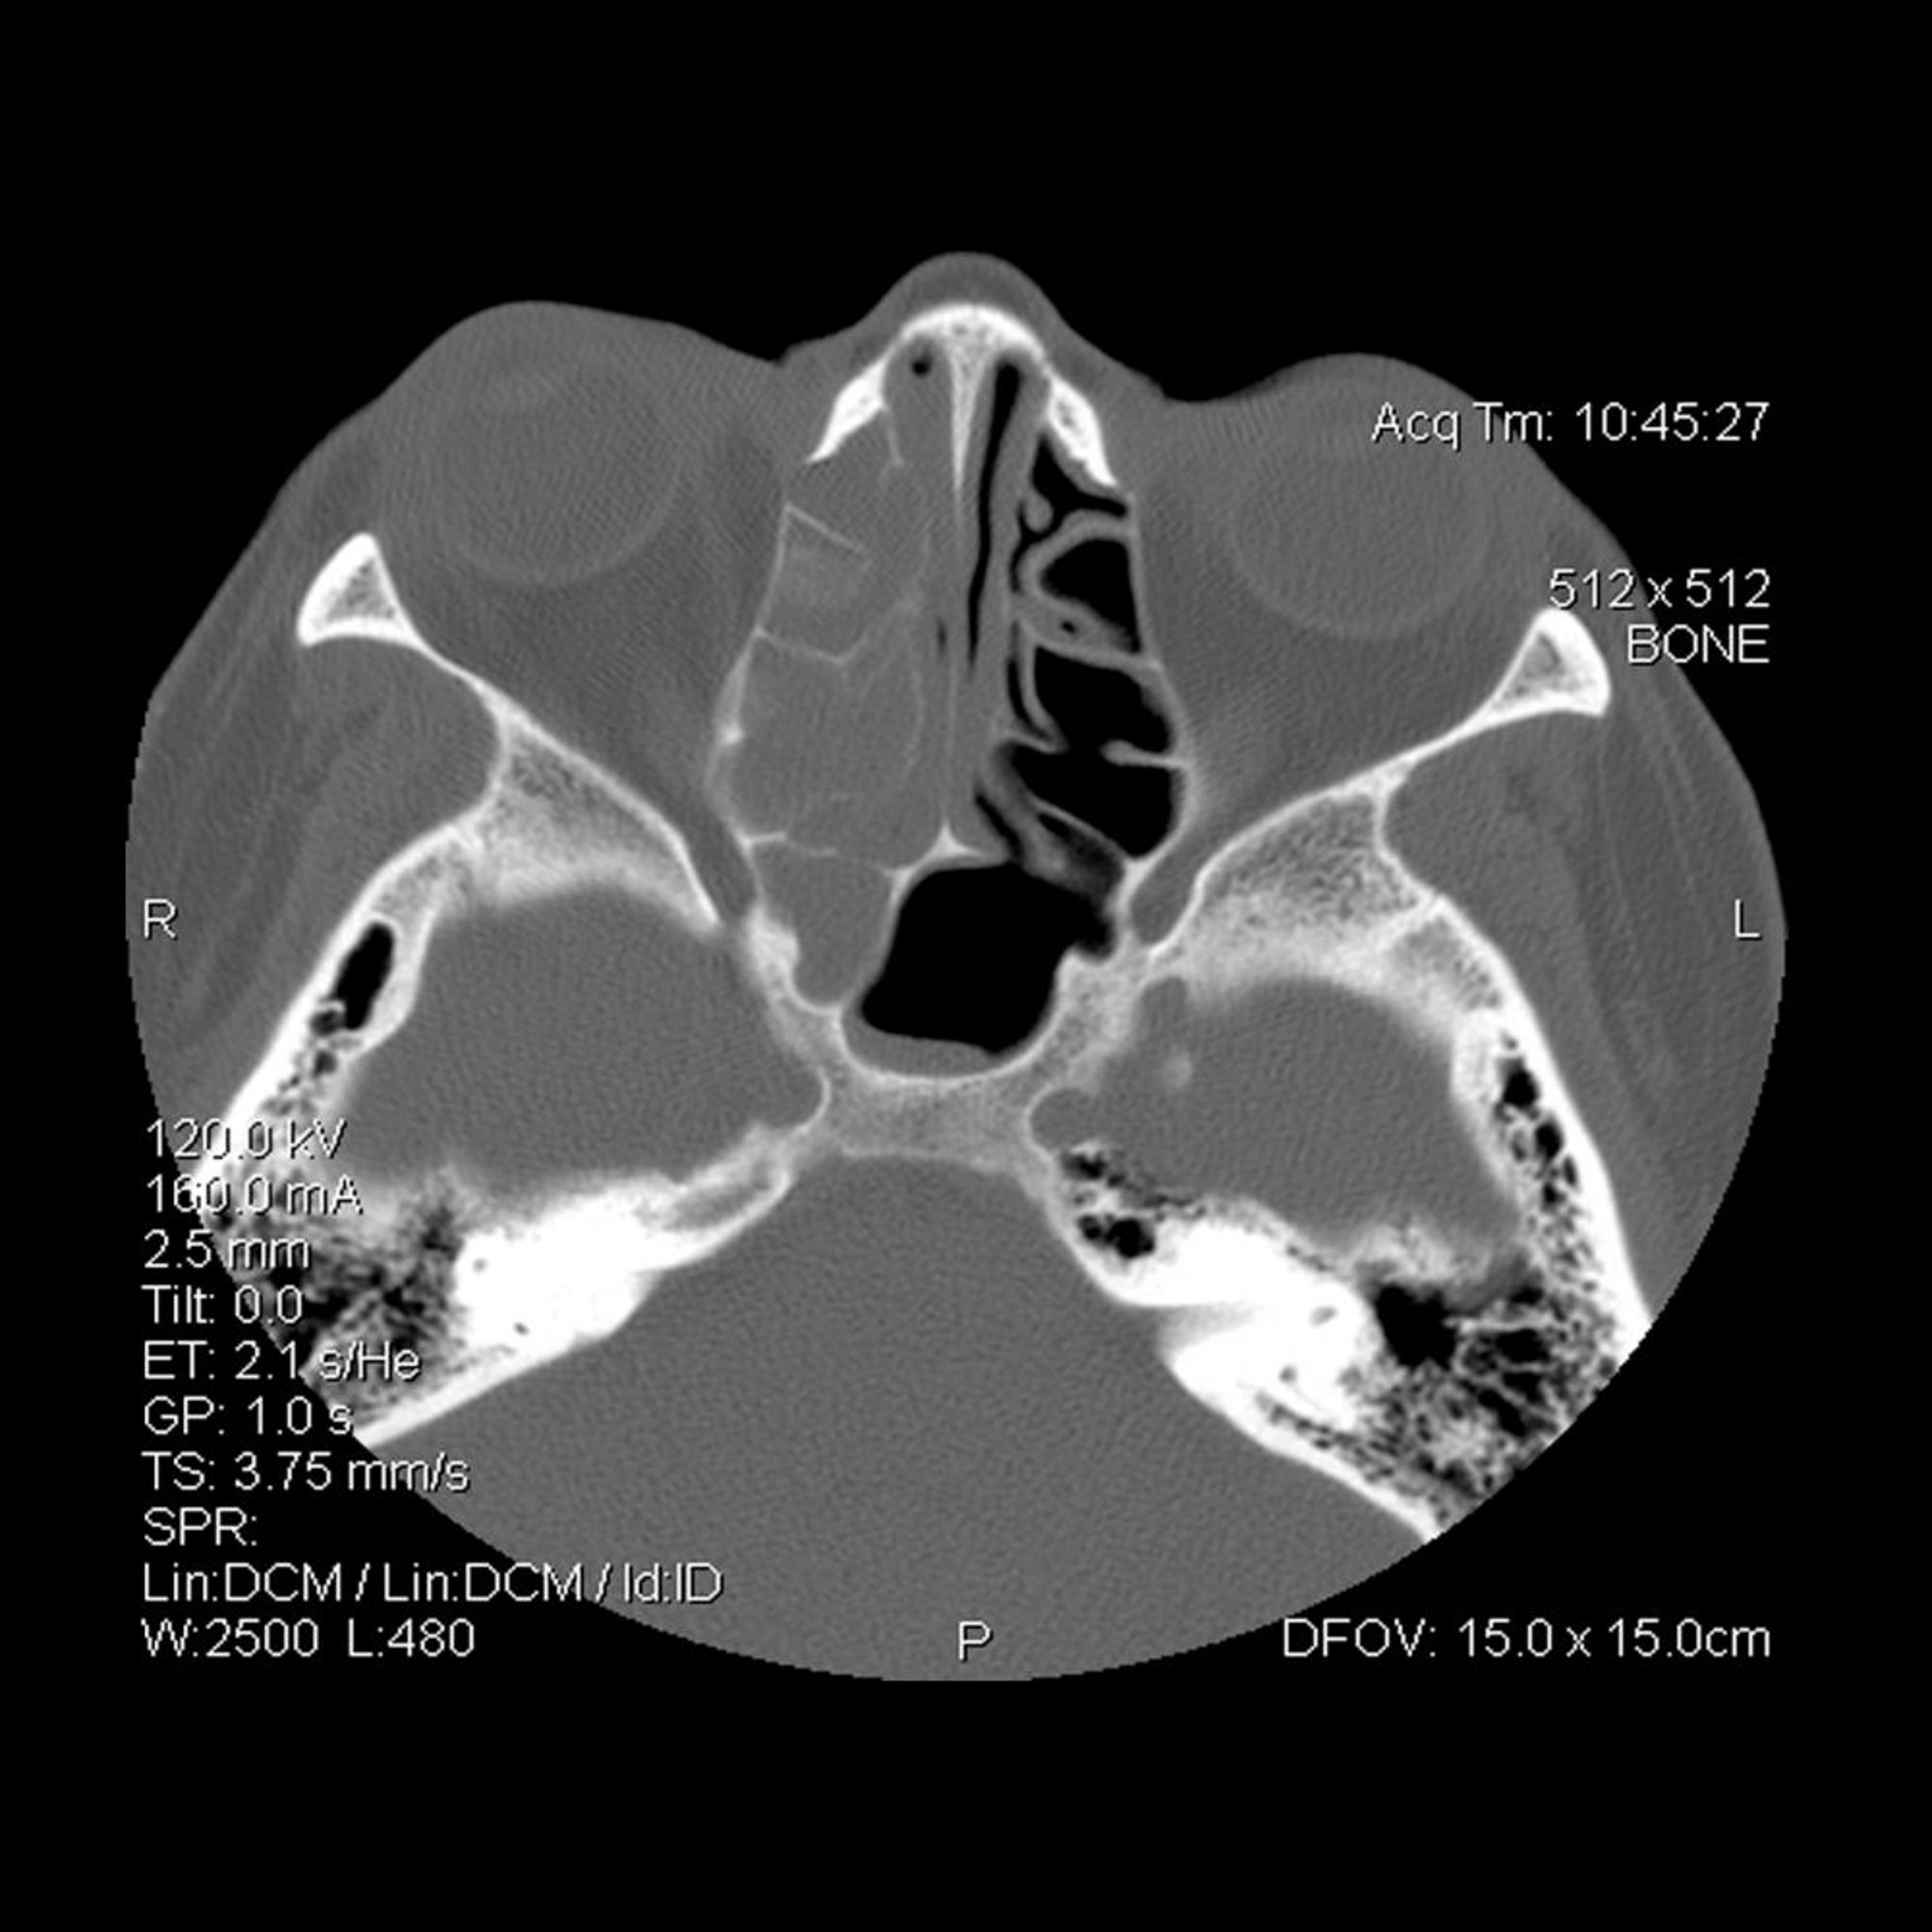

Opacification of the right (on viewer's left) ethmoid and sphenoid sinuses.